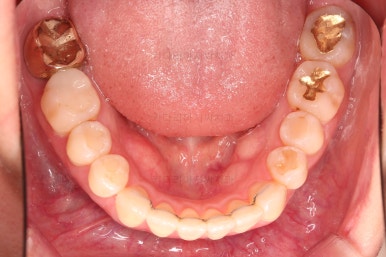

3. 치료과정

개방교합을 닫는 전략은 앞니를 약간 끌어내리고, 어금니를 앞니 위치로 약간 올려서 균형을 맞추는 건데요.

장치 부착은 윗니 어금니부터 했습니다.

미니스크류를 다양하게 활용하여 어금니 높이를 조절합니다.

여전히 앞니는 내버려둔 채로, 윗니는 어금니쪽만 진행하며 아랫니도 장치를 부착했습니다.

난이도가 매우 높은 치료인만큼 미니스크류의 구성과 장치 구성도 매우 복잡했는데요.

윗니 어금니를 뒤로 밀면서 앵글씨 2급 부정교합을 개선해 주고, 높낮이를 조절하면서 개방교합을 개선해 줍니다.